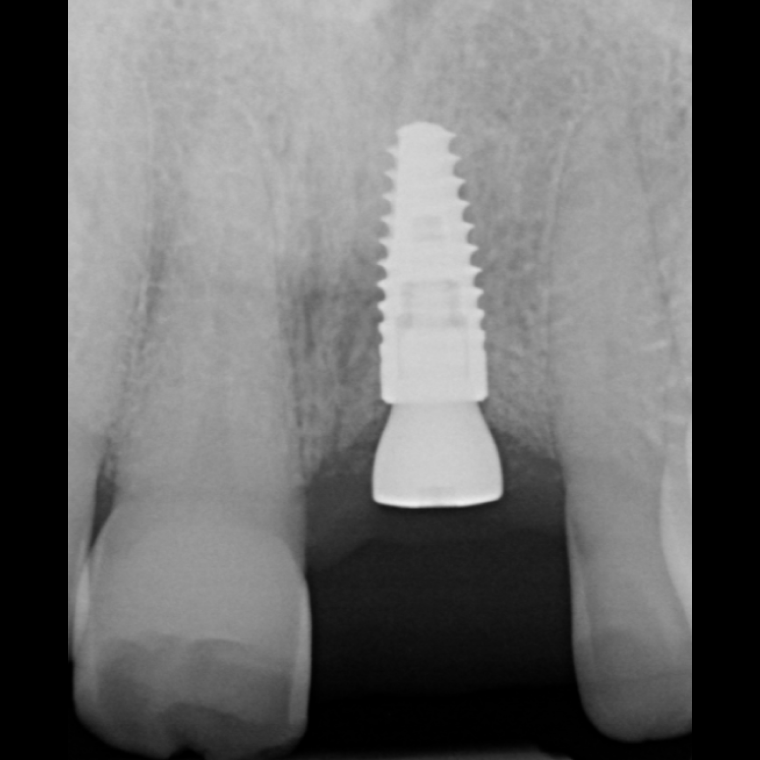

Socket Preservation for implant

Before

Extraction of 21

After

Socket Graft of 21:

3 Months

3 Months

Implant 21

Socket Preservation for implant

Before

Extraction of 21

After

Socket Graft of 21: 3 Months

Implant 21